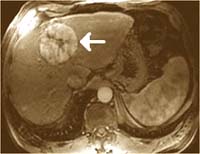

-  !important; Chụp CT scanner bụng có bơm thuốc tĩnh mạch cho thấy khối kích thước 6.0 × 5.0 × 4.0cm, nhiều vùng có tính chất hoại tử, không đồng nhất, giảm âm ở gan (P) lan rộng từ giữa ra ngoại vi, bờ và đến cả vỏ bao gan. Khối tổn thương này phân chia thành ngăn (septation) có xuất huyết nhu mô xung quanh.

Xem lại hình ảnh CT scan biểu hiện cùng các xét nghiệm trên, gợi ý là bệnh cảnh một nang nước (hydatid cyst) tồn tại bởi vì không có vỏ hoặc hình ảnh calci hóa, xuất hiện hình ảnh xuất huyết trong khoang. Chụp CT lại không thay đổi. Kết quả xét nghiệm huyết thanh cho amíp và Western blot cho Echinococcus đều (-), mẫu phân chứa Blastocystis hominis và Endolimax nana. Xét nghiệm huyết thanh với kháng thể Fasciola hepatica âm tính (FAST-ELISA);

Tuần tiếp theo, đếm eosin tăng lên 7.000/mm3 (46%) và dần dần giảm sau đó. Chụp cộng hưởng từ (MRI) cho thấy hình ảnh một u mạch hoặc u tuyến ở gan vỡ. Tuy nhiên, số lượng hồng cầu đã cho phép loại trừ. Test miễn dịch huỳnh quang gián tiếp (IIF_Indirect immunofluorescence ) kháng thể với Fasciola hepatica 1-2 tuần sau đó cũng âm tính với xét nghiệm FAST-ELISA, chỉ có hiệu giá kháng thể tăng lên 1:80 và 1:160 (1:20 là giới hạn ngưỡng [+]). Kết quả của điện di miễn dịch cũng dương tính, cho thấy 3 dải băng trên mẫu huyết thanh thứ nhất và 4 băng trên dải huyết thanh thứ 2. Bệnh nhân được điều trị bẳng thuốc đặc hiệu triclabendazole, liều duy nhất (10 mg/kg, 700mg), biệt dược Fasinex của hãng Novartis, Basel, Switzerland). Một kết quả chẩn đoánCT-scan 12 tuần sau đó cho thấy hầu như tổn thương đã được giải quyết hoàn toàn. Xét nghiệm phân cũng âm tính với F. hepatica ở tuần thứ 16. Triệu chứng của bệnh nhân không tái phát và đếm bạch cầu eosin cũng như xét nghiệm cận lâm sàng khác đều trở về bình thường. Một năm sau kiểm tra lại tất cả đều bình thường cả lâm sàng, cận lâm sàng và chẩn đoán hình ảnh.